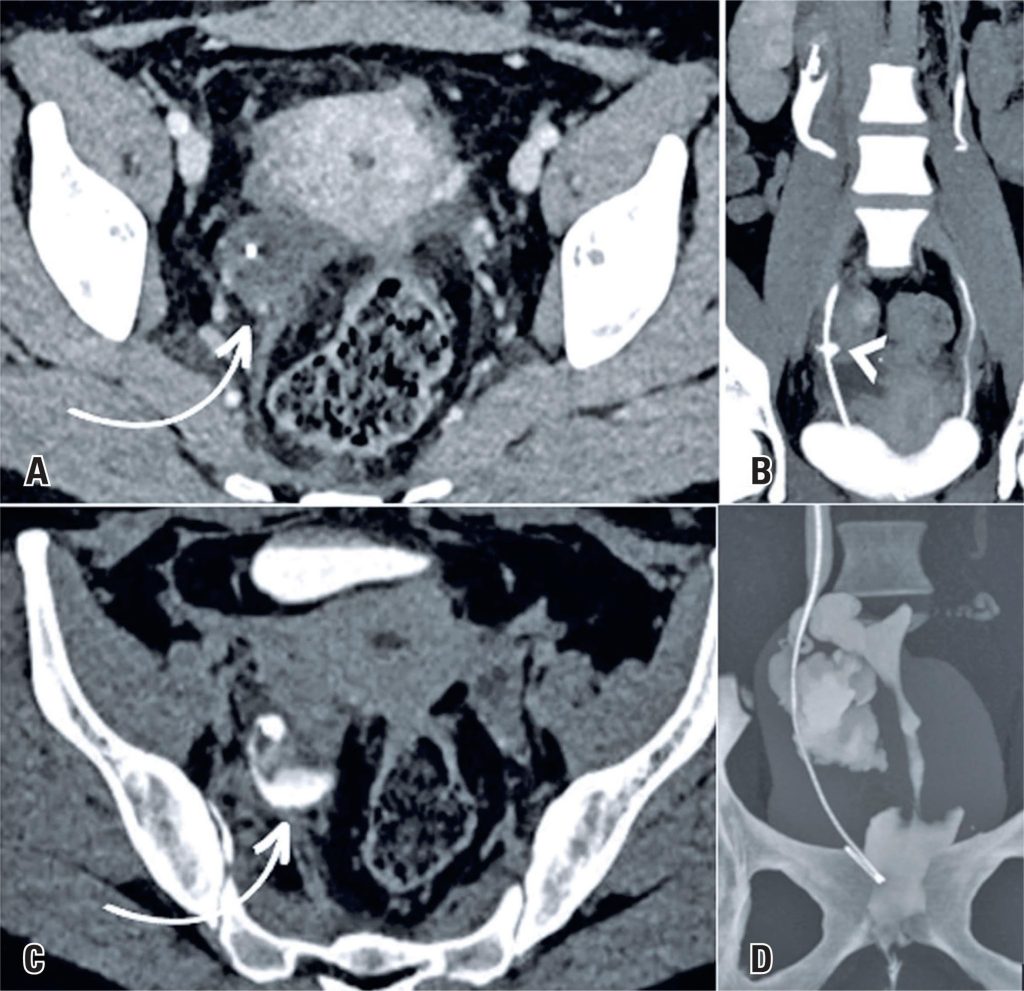

Uretero-fallopian fistula after gynecological surgery for endometriosis: a case report

The increasing use of videolaparoscopy for the complete excision of endometriotic lesions and restoration of pelvic anatomy has helped improve long-term outcomes. However, risks remain, including rare but significant complications such as salpingoureteral fistulas. Early diagnosis using imaging methods enables adequate treatment and reduces the risk of new complications. In this report, we present a case of uretero-fallopian fistula following gynecological surgery for the resection of endometriotic lesions, with intraoperative inadvertent ureteral injury. This case report aimed to highlight the importance of diagnostic imaging in postoperative complications of gynecological surgeries for endometriosis, especially if inadvertent injuries occur during the procedure, and to guide the medical community in suspecting and addressing this condition.